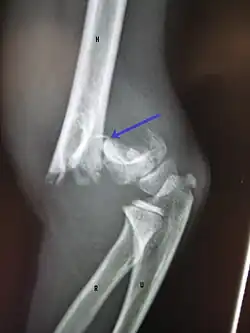

A displaced supracondylar fracture in a child

Distal humerus fractures usually occur as a result of physical trauma to the elbow region. If the elbow is bent during the trauma, then the olecranon is driven upward, producing a T- or Y-shaped fracture or displacing one of the condyles.[7]

Definitive diagnosis of humerus fractures is typically made through radiographic imaging. For proximal fractures, X-rays can be taken from a scapular anteroposterior (AP) view, which takes an image of the front of the shoulder region from an angle, a scapular Y view, which takes an image of the back of the shoulder region from an angle, and an axillar lateral view, which has the patient lie on his or her back, lift the bottom half of the arm up to the side, and have an image taken of the axilla region underneath the shoulder.[9] Fractures of the humerus shaft are usually correctly identified with radiographic images taken from the AP and lateral viewpoints.[12] Damage to the radial nerve from a shaft fracture can be identified by an inability to bend the hand backwards or by decreased sensation in the back of the hand.[5] Images of the distal region are often of poor quality due to the patient being unable to extend the elbow because of pain. If a severe distal fracture is suspected, then a computed tomography (CT) scan can provide greater detail of the fracture. Nondisplaced distal fractures may not be directly visible; they may only be visible due to fat being displaced because of internal bleeding in the elbow.[7]